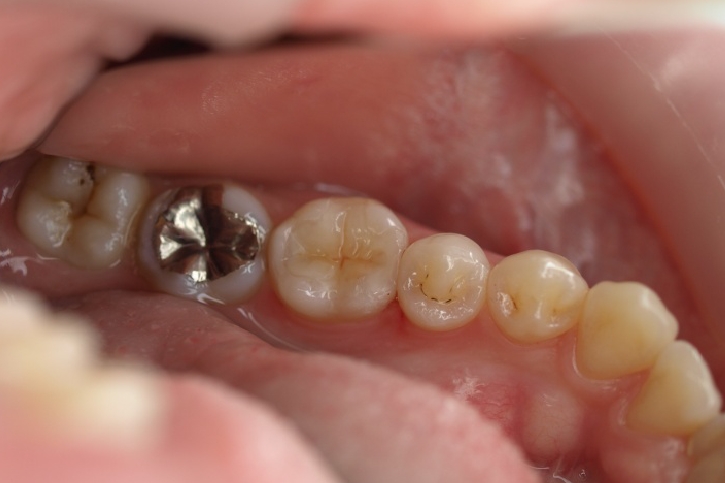

2013年3月2日千葉市中央区 S.K様 左下6番 ハイブリッドセラミックインレー修復

ハイブリッドセラミックス修復

担当歯科医師:丸林浩太郎